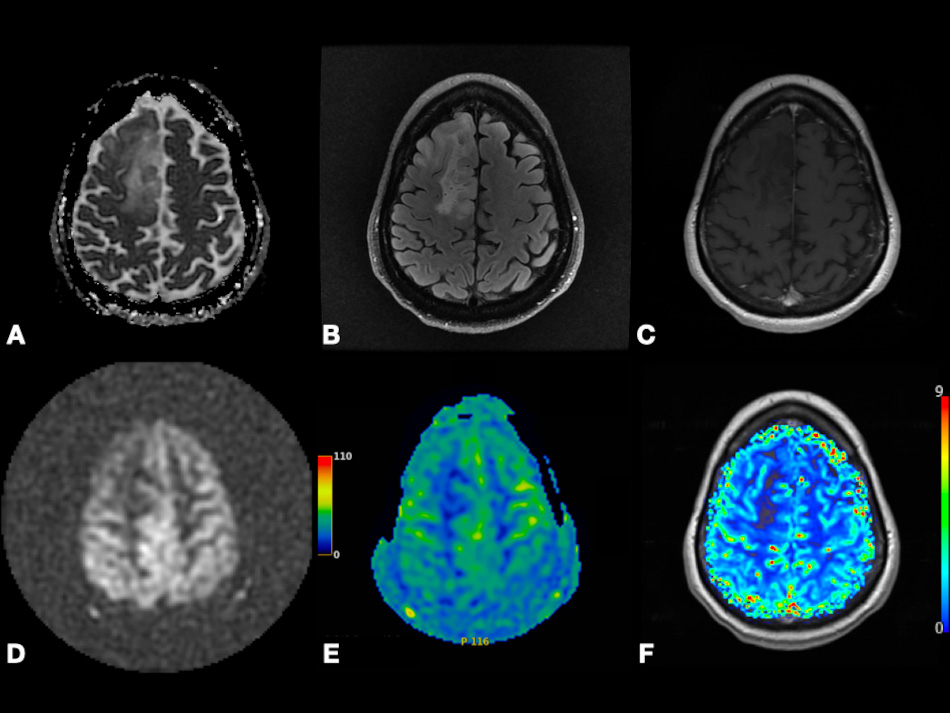

In contrast to conventional MRI, which delineates the anatomical structures and shows gross changes in the structure of the tumor, advanced MRI techniques represent dynamic physiological properties of tissue, which may be helpful in differentiating undiagnosed lesions based on properties including vascularity, cellularity, and metabolism [7, 8, 9]. The term advanced MRI techniques is used throughout this article to refer to dynamic contrast-enhanced (DCE) MRI, dynamic susceptibility contrast (DSC) MRI, diffusion-weighted imaging (DWI), arterial spin labeling (ASL) MRI, and blood oxygen level-dependent functional MRI (BOLD fMRI). In Figs. 1,2, we present different MRI images of two cases with different brain lesions including right frontal lobe oligodendroglioma (WHO grade II) and left lateral ventricle cavernous malformation. These two figures demonstrate the main differences between conventional MRI which delineates the anatomical borders of the brain lesions and advanced MRI techniques which demonstrate the internal physiologic features of different tumors, such as their vascularity, cellularity, perfusion, oxygenation, and microstructure.

Fig. 1.Right frontal lobe oligodendroglioma (WHO Grade 2). Axial ADC map (A), FLAIR (B), and post-contrast T1-weighted (C) images depicting non-enhancing tumor with T2 prolongation in gray and white matter and increased diffusivity (i.e., shine-through artifact). Axial pcASL source data (D), color-coded CBF map (E) from pcASL data, and color-coded rCBV map (F) from DSC data depicting no hyperperfusion. Abbreviation: ADC, Apparent diffusion coefficient; FLAIR, Fluid attenuated inversion recovery; pcASL, Pseudo-Continuous Arterial Spin Labeling; CBF, cerebral blood flow; rCBV, relative cerebral blood volume; DSC, Dynamic susceptibility contrast MR imaging.